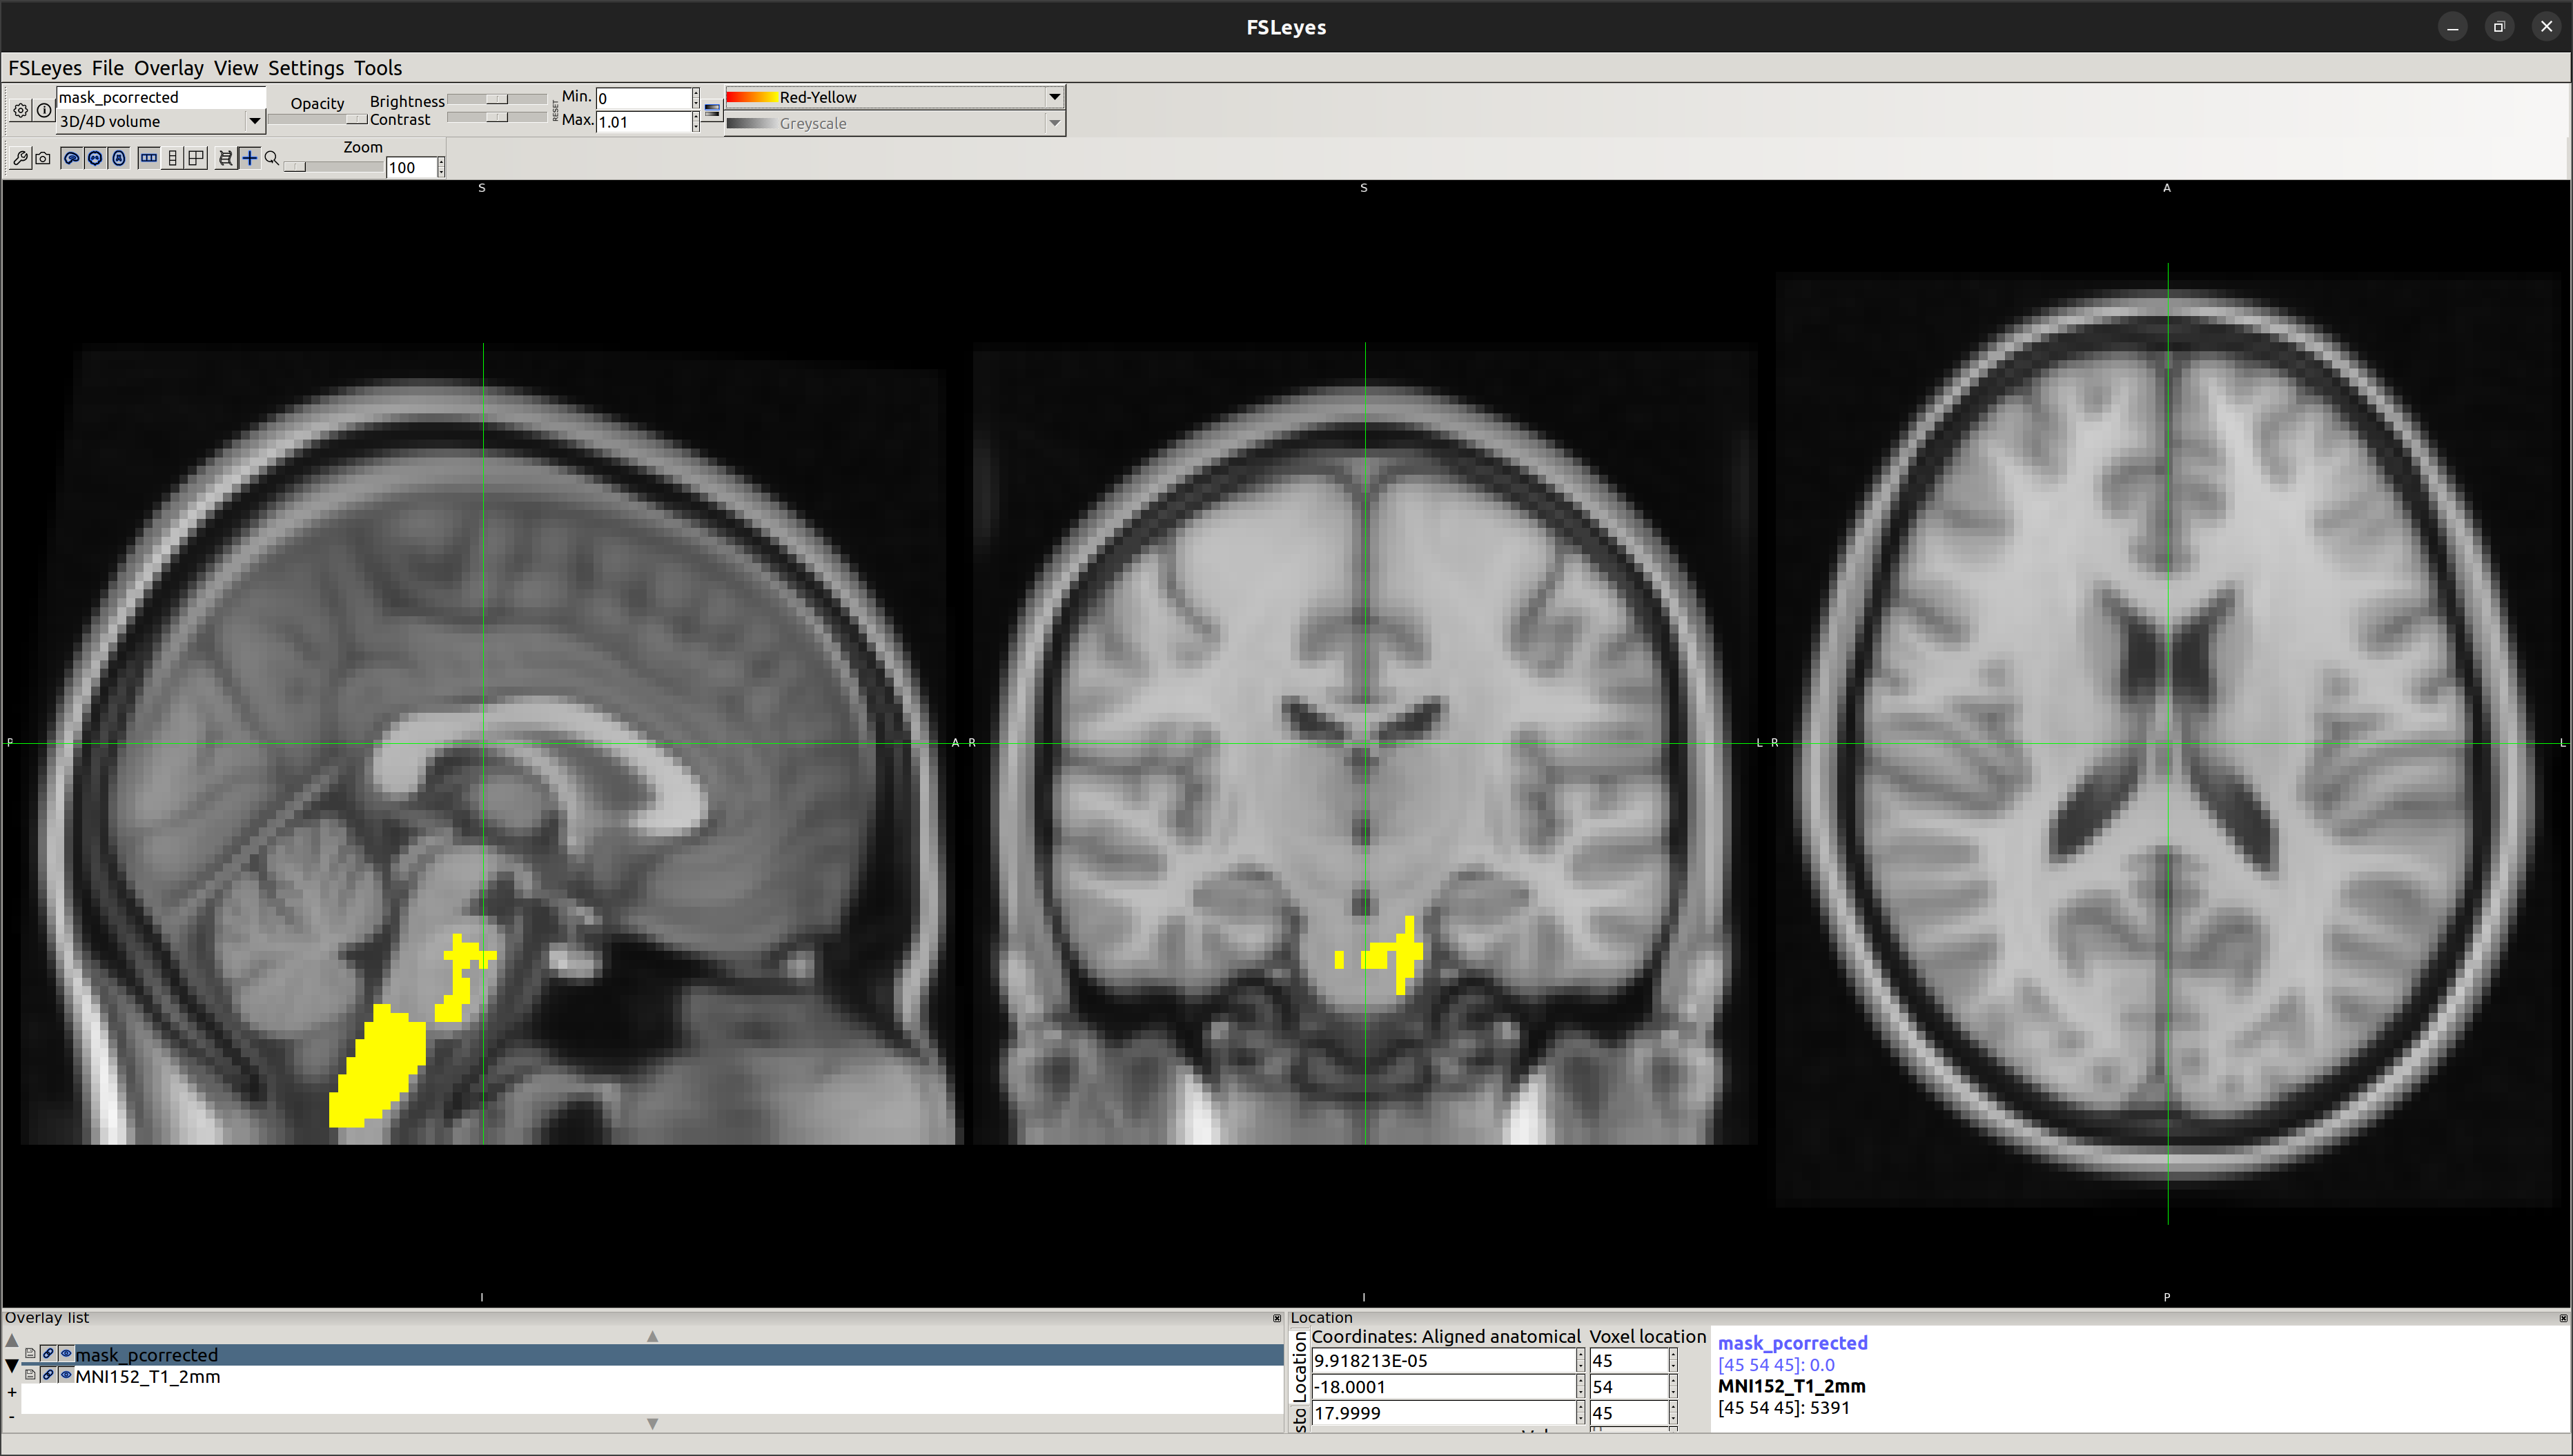

NonAth>AmFB

Showing the local differences in grey matter volume between the two groups:

To obtain statistical data, identify the region of significant difference and validate that:

[1] E2 - Running randomise and displaying cluster-based thresholding results

Reference: https://fsl.fmrib.ox.ac.uk/fsl/fslwiki/FSLVBM/UserGuide